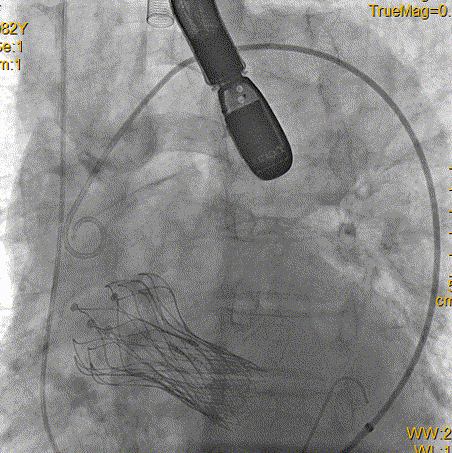

右侧股动脉造影

左侧股动脉造影